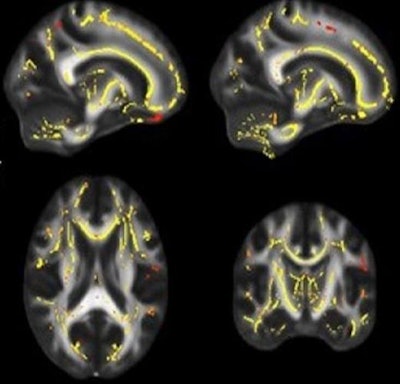

All participants underwent a battery of tests, including DTI to assess white-matter fiber integrity, a method known as maximal oxygen uptake to measure the subjects' cardiorespiratory fitness, and memory and other cognitive tests to measure brain function. By doing so, the researchers aimed to determine correlations between exercise, brain health, and cognition.

They found that lower fitness levels were associated with weaker white matter, which in turn correlated with lower brain function.